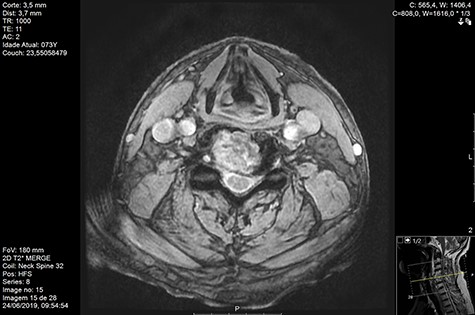

MRI and CT scans performed at 90 days post-radiation therapy showed an arrest of further progression of instability and resolution of the lytic lesion (Figs 7–13).